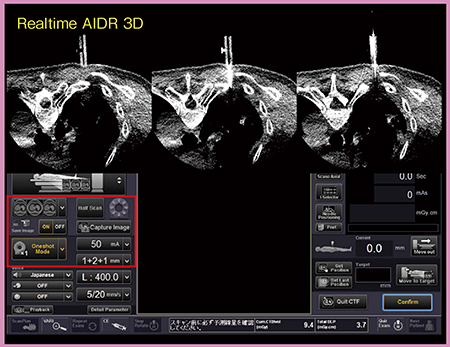

320列の最新型Angio CTは,CTガイド下手技において,リアルタイムに“AIDR 3D”を適用した3断面透視画像に加え,モード切り替えにより穿刺やドレナージ,生検など,さまざまなシーンで利用できるように工夫が施されている。当院導入後の503件の検査のうち,18%でCTガイド下手技(生検,マーカー留置,凍結療法,ドレナージ術)を実施している。

1.肺生検

肺生検における3断面透視の実際のモニタ画面を図5に示す。モードの切り替えは,画面左下のボタン(図5□)で容易に行うことができ,通常の肺生検などではOneshot Modeで穿刺を進め,腫瘍に近づいたらContinuous Modeに切り替えるといった使い方をしている。Oneshot Modeではhalf scanを利用することで,術者の被ばく線量を低減することができる。

また,AIDR 3Dを適用することで,ノイズの少ない3断面透視画像ガイド下に手技を行うことができる。肺はコントラストが非常につきやすいが,実質臓器内の腫瘍や大きな腫瘍のどの部分をねらって穿刺するかを判断する場合などには,AIDR 3Dを適用することでコントラストが向上し有用である。

図5 肺生検における3断面透視画面